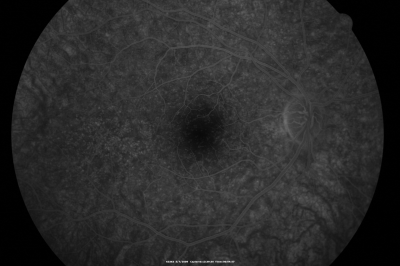

Basal Laminar Drusen - Cuticular Drusen - 19 Year Old with Lupus Nephritis

19-year-old.  She has a history of developing severe systemic lupus erythematosus in 2001.  She was in renal failure and had biopsy proven Class 2 lupus nephritis.  She is currently on Plaquenil 400 mg for six years, as well as Prednisolone orally, every other day. OD 20/20, OS 20/25.